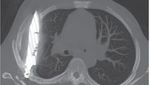

Jakarta - Begini penampakan pisau yang menancap di dada seorang pria di Tanzania. Pasien baru menyadari di tubuhnya ada pisau 8 tahun kemudian.

Foto-foto Penampakan Pisau Menancap di Dada, Pasien Sadar Setelah 8 Tahun